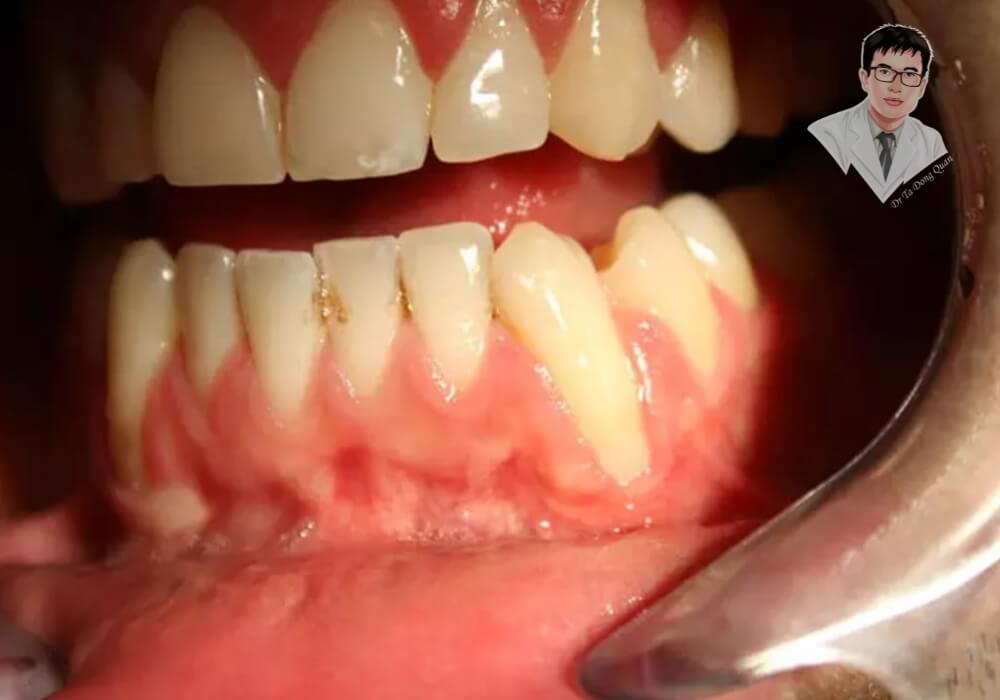

Tụt nướu răng là tình trạng mô nướu bị co rút, làm lộ chân răng và tạo khoảng trống giữa răng và nướu. Điều này khiến vi khuẩn dễ xâm nhập, làm tăng nguy cơ sâu răng, viêm nha chu và có thể dẫn đến mất răng nếu không được điều trị kịp thời. Không chỉ ảnh hưởng đến sức khỏe răng miệng, tụt nướu còn làm giảm thẩm mỹ, khiến răng trông dài hơn và dễ bị ê buốt khi tiếp xúc với thực phẩm nóng, lạnh.

2. Bệnh nha chu

Viêm nướu và viêm nha chu là những bệnh lý nghiêm trọng ảnh hưởng đến mô nướu và xương nâng đỡ răng. Khi vi khuẩn tích tụ quá mức, chúng gây viêm nhiễm, làm suy yếu nướu và khiến nướu dần tụt xuống. Nếu không được điều trị kịp thời, viêm nha chu có thể gây tiêu xương, làm răng lung lay và tăng nguy cơ mất răng.

2. Nướu chảy máu thường xuyên và đau nhức kéo dài

Chảy máu nướu khi đánh răng hoặc ăn uống là dấu hiệu cho thấy mô nướu đang bị viêm. Nếu tình trạng này diễn ra thường xuyên kèm theo đau nhức kéo dài, có thể bạn đang mắc bệnh viêm nha chu hoặc viêm nướu. Việc điều trị kịp thời giúp ngăn chặn vi khuẩn lan rộng, bảo vệ nướu khỏi nguy cơ tổn thương nặng hơn.